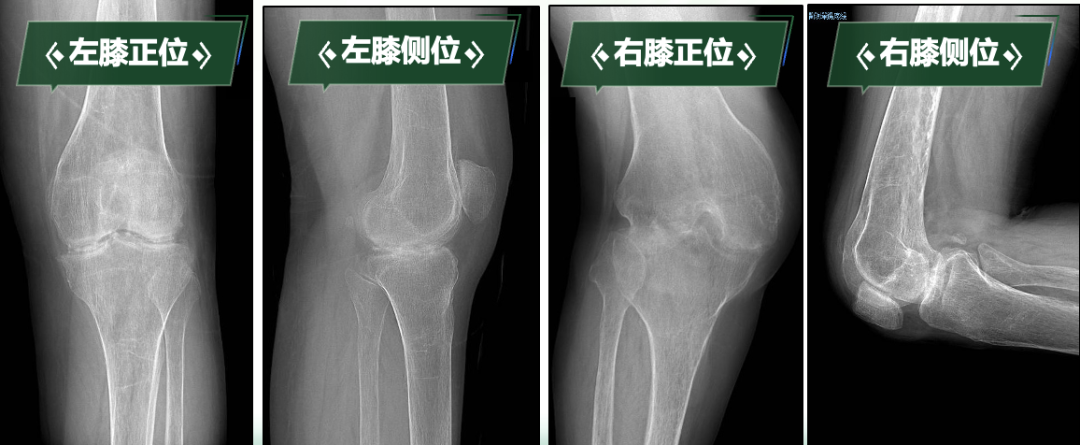

下肢处于功能“锁死”状态的刘阿姨,不仅被剥夺了行走能力,还导致严重肌肉萎缩、骨质疏松,生活质量急剧下降,手术是帮助她重新站起来的唯一途径。科室高度重视,经多学科会诊讨论,制定周密治疗规划。曹晓瑞副主任医师团队分析术前影像学资料,精确评估膝关节骨质破坏、关节融合及周围软组织条件。

手术关键难点在于精准截除融合骨组织、获得屈伸间隙平衡、恢复下肢力线、确保韧带平衡以重建膝关节功能。团队凭借丰富经验和娴熟技术,成功实施双侧人工全膝关节置换术。术后影像学检查显示,假体位置精准,下肢力线完美纠正,原本僵硬关节被活动自如的人工关节取代,患者功能恢复理想,能正常行走,生活质量显著改善。